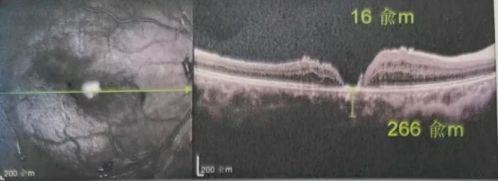

去年年底,年逾7旬的吳爺爺突然發(fā)現(xiàn)右眼看不清,且看東西變形,到當(dāng)?shù)蒯t(yī)院檢查后確診黃斑裂孔。此后他輾轉(zhuǎn)求醫(yī),經(jīng)歷了兩次玻切聯(lián)合內(nèi)界膜剝除術(shù),每次術(shù)后都嚴(yán)格“趴睡”一個(gè)月。然而結(jié)果令人失望:裂孔不但沒閉合,反而持續(xù)擴(kuò)大,甚至還并發(fā)高眼壓。

由于自身患有頸椎病,每次術(shù)后長期的趴睡都讓他痛苦不堪。為了尋求更好的治療,吳爺爺來到廈門大學(xué)附屬廈門眼科中心,找到了眼外傷及眼底病2科的李海波博士后。此時(shí),吳爺爺右眼的黃斑裂孔已經(jīng)持續(xù)擴(kuò)大到780μm,演變?yōu)殡y治性的大裂孔。

最讓吳爺爺難以置信的是:術(shù)后只需保持平躺24小時(shí)!第二天復(fù)查時(shí),眼底鏡及OCT檢查清晰顯示——那個(gè)折磨了他大半年的大裂孔,竟然閉合了!且吳爺爺?shù)挠已垡暳τ辛嗣黠@的改善,術(shù)后3天已經(jīng)可以看到 0.15。